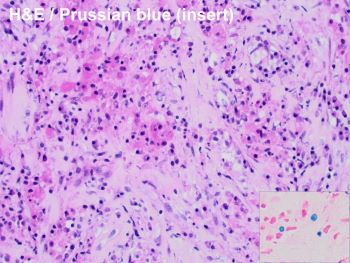

A 59-year-old female with a history of ESRD attributed to hypertension, a renal transplant in 2004 on maintenance immunosuppression. Admission for E. coli sepsis with severe AKI a month prior; now with uremic symptoms, creatinine 6.0 mg/dL (baseline 1.9), normal renal ultrasound. Allograft biopsy shown.

The images of the biopsy show the characteristic features of malakoplakia with obliteration of the renal cortex by a diffuse interstitial inflammatory infiltrate mainly composed of histiocytes with granular eosinophilic cytoplasm. Many of these histiocytes contain targetoid structures positive for PAS, calcium and iron diagnostic of Michaelis Gutman bodies. These represent laminated mineralized concretions that result from the deposition of calcium in phagolysosomes overloaded with breakdown products of bacteria.

Malakoplakia (which means “soft plaque” based on the clinical appearance), is a rare inflammatory disorder that most commonly affects the genitourinary system of women. When affecting the kidney, it is associated with a history of urinary tract infections, most frequently Escherichia coli. The pathogenesis of the disease is thought to be due to a defect in the phagocytic function with incomplete clearance of bacterial organisms in patients with disorders of the immune system, or immunosuppressed states. The latter includes solid transplant patients, such as in this case, where the malakoplakia may compromise allograft function and could result in graft loss. Early diagnosis and prompt start of treatment are essential.

Although there are no guidelines or standard criteria for management, treatment modalities in the setting of renal transplantation include antimicrobial therapy (correct answer B), surgical or radiological debulking and reduced immunosuppression. Successful outcomes have been reported with a combination approach of use of antibiotics with intracellular activity along with immunosuppression reduction. Plasmapheresis is a treatment option for patients with antibody mediated rejection, increased immunosuppression is contraindicated in these patients, and chemotherapy may be used in the treatment of malignant neoplasms, which malakoplakia can mimic clinically and radiologically.